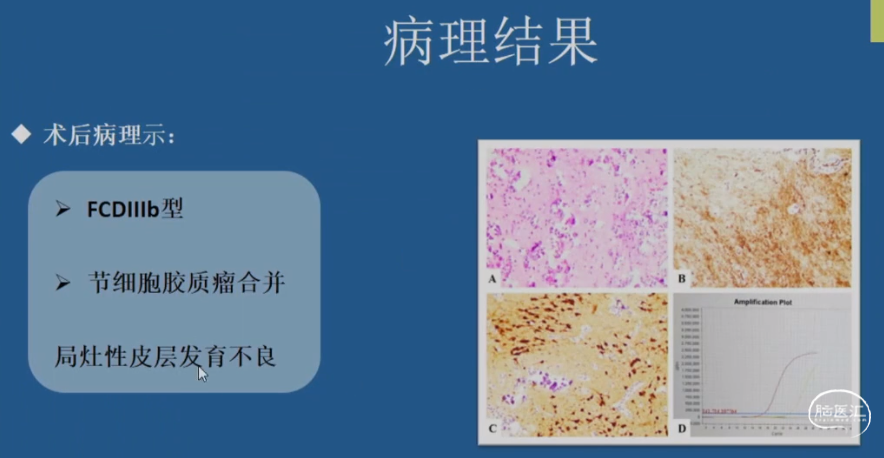

结构性病因诊断

•神经节细胞胶质瘤Gangliogliomas(GG)

•归类:神经元和神经元-神经胶质肿瘤类,WHO Ⅰ级

结构性病因诊断

•局灶性皮质发育不良(FCD)Ⅲb型